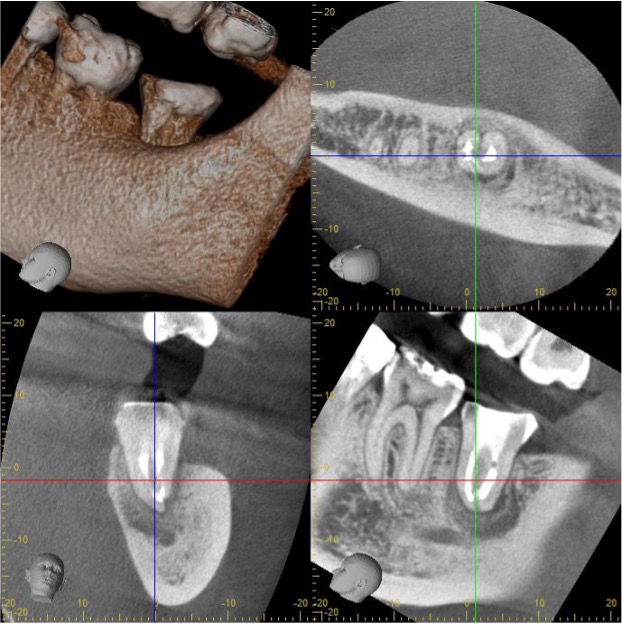

広範囲の骨吸収を認める再治療 (メタルポスト除去)

- 主訴

- 前歯の歯茎が腫れて痛い

- 治療内容

- 左上側切歯

根尖性歯周炎

太くて長いメタルの土台が装着されており、CT所見では広範囲の周囲骨が炎症により破壊、吸収されている。

唇側と口蓋側の両方とも骨吸収を認め、強い炎症と反応が予測できる。

また、隣の歯にまで骨吸収が及んでいた。

3ヶ月後のCT検査で、病変の縮小と、骨の再生が認められた。

もし、治癒が認めれなければ、外科的なアプローチが必要になった症例です。

- 治療期間

- 2回

- 治療のリスク

- 太くて長いメタルの土台を外す際に、健康歯質の過度な切削を起こさせないこと。

除去時にかかる力や器具操作のストレスで、歯の破折などを生じさせないように注意を払った。

土台の接着材料や、土台の種類によっては安全な除去が困難であることがあり、その場合は外科的なアプローチで病変へのアプローチをすることを、患者様と話し合った。

BEFORE

AFTER